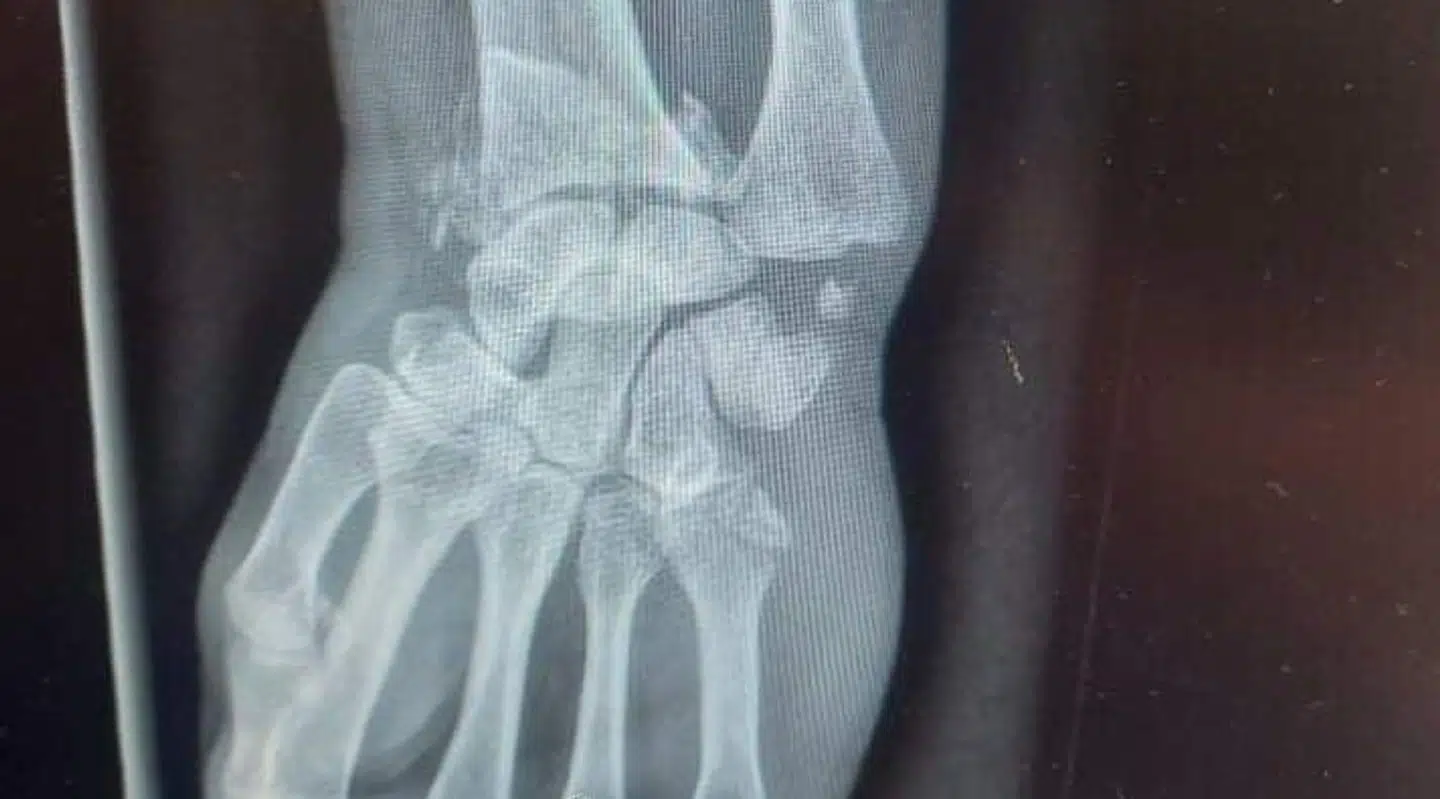

Dorthe Madsen brækkede sit håndled tre steder.

På sygehuset bliver det konstateret, at hun har brækket sit håndled tre steder og fået ødelagt en sene i hånden. Dagen efter ulykken bliver hun opereret, og nu går hun sygemeldt derhjemme – med god tid til at tænke hele forløbet igennem.